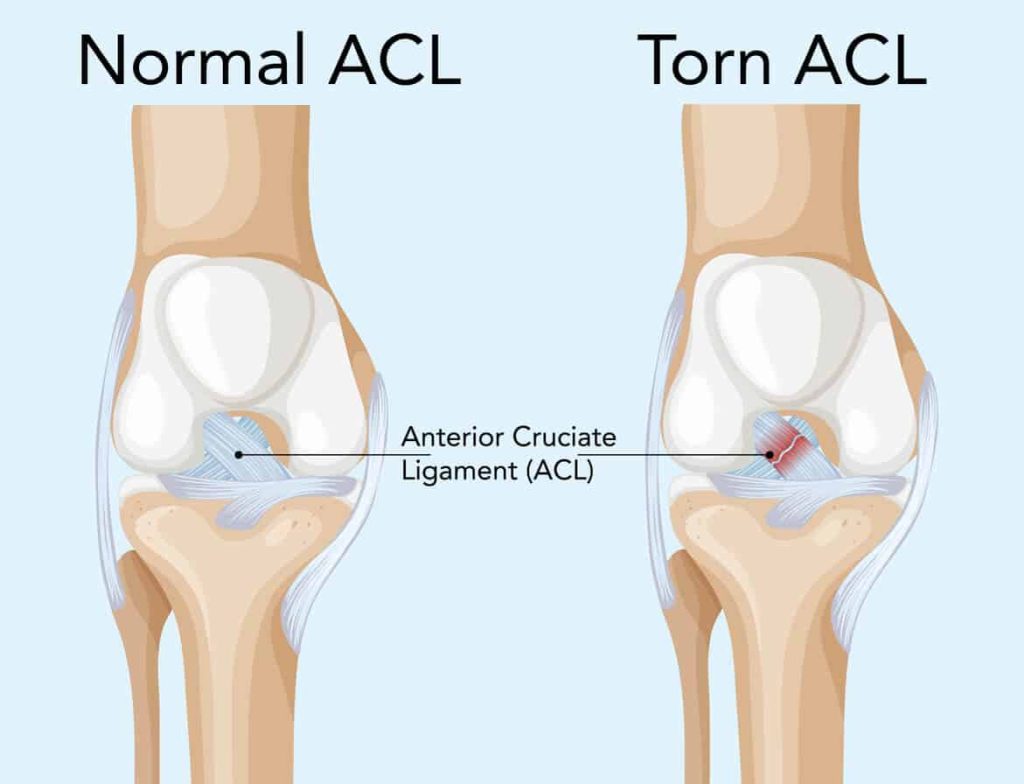

ACL ialah ligamen penting di dalam lutut yang menyambungkan tulang paha (femur) ke tulang betis (tibia). Ia berfungsi untuk mengawal pergerakan hadapan tibia dan memberikan kestabilan pada sendi lutut.

Apabila ligamen ini diregang atau terkoyak, ia dikenali sebagai Acl Injury. Punca utama kecederaan ini termasuk:

ACL Injury boleh menyebabkan lutut terasa tidak stabil dan memberi risiko kecederaan lebih serius jika tidak dirawat dengan betul.

ACL Injury sering menyebabkan kehilangan fungsi proprioception iaitu keupayaan badan untuk “rasa” posisi lutut dalam ruang. Ini boleh mengakibatkan lutut mudah terkilas atau “give way”.